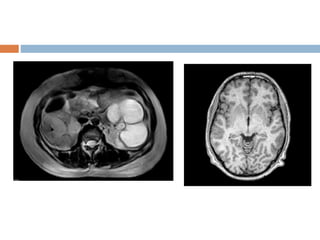

Chemical shift artifact

 In the frequency direction, the MR scanner uses

the frequency of the signal to indicate spatial

resolution

 Since water in organs and muscles resonate at

different frequency than fat.

 The MR scanner mistakes the frequency as a

spatial difference.

 Commonly noticed in vertebral end plates,

abdomen, and orbits where fat and other tissues

form borders.

 Appearance

 Spine -one end plate to appear thicker than

the opposite one.

 Abdomen &orbits -Black border at fat water

interfaces and bright border at opposite

border.

 Solution

fat suppression technique

Use wide receiver bandwidth

Chemical shift artifact In the frequency direction, the MR scanner uses the frequency of the signal to indicate spatial resolution  Since water in organs and muscles resonate at different frequency than fat.  The MR scanner mistakes the frequency as a spatial difference.  Commonly noticed in vertebral end plates, abdomen, and orbits where fat and other tissues form borders.

 Appearance  Spine-one end plate to appear thicker than the opposite one.  Abdomen &orbits -Black border at fat water interfaces and bright border at opposite border.  Solution fat suppression technique Use wide receiver bandwidth